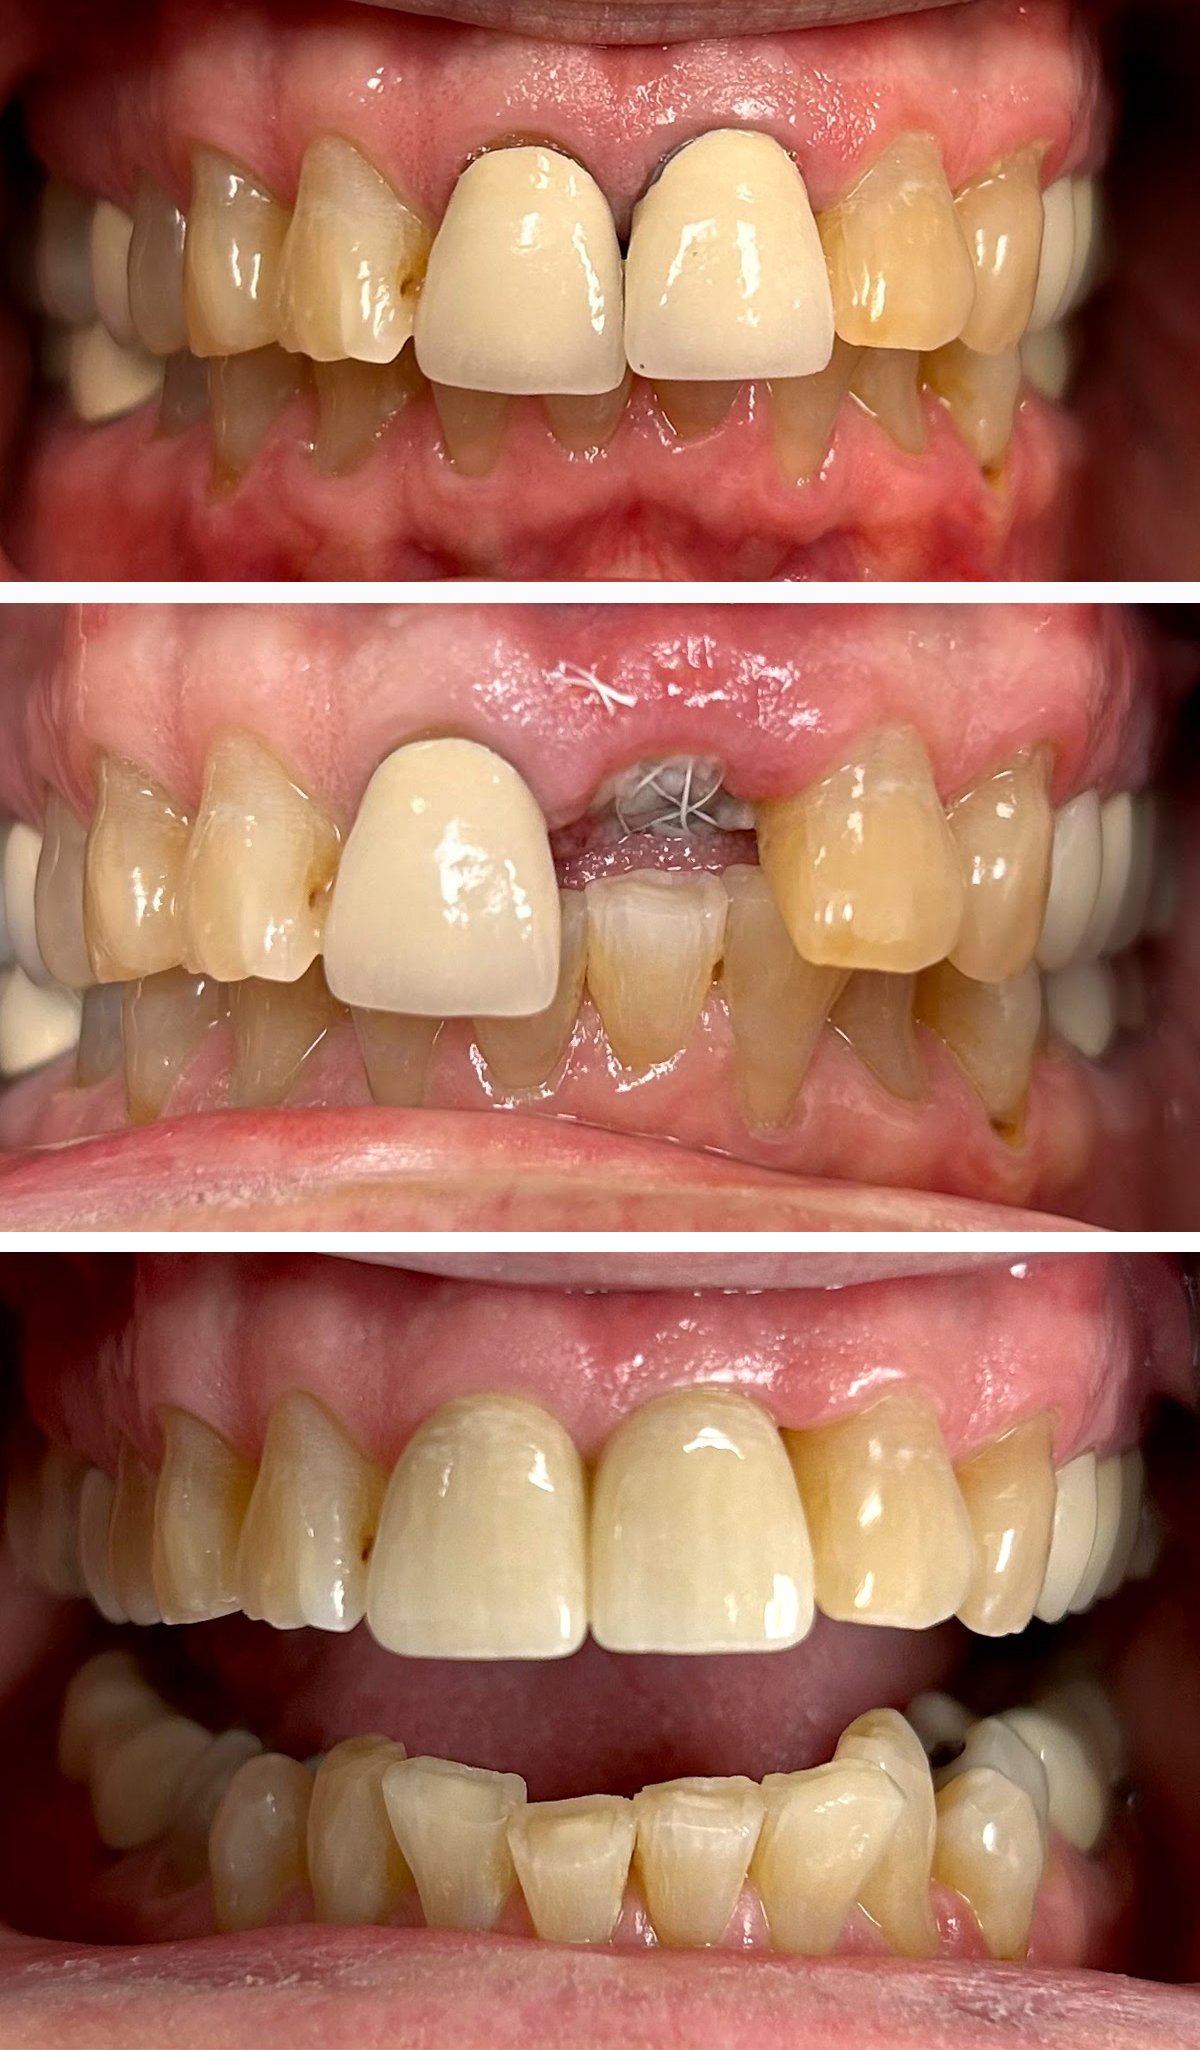

Before and after implant placement of front tooth, restored with custom crown

Tooth replacement with implant and crown